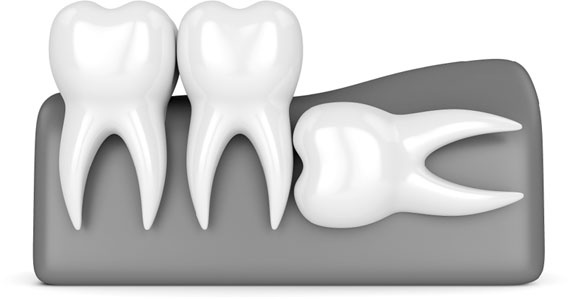

Иллюстрация к книге — Злые зубы [i_032.jpg]

А на этом снимке наглядно видно, как «восьмерки» повреждают «семерки». Зачастую при такой ситуации уже глубокий кариес корня седьмых зубов и их приходится удалять вместе, так как, к сожалению, уже не спасти.